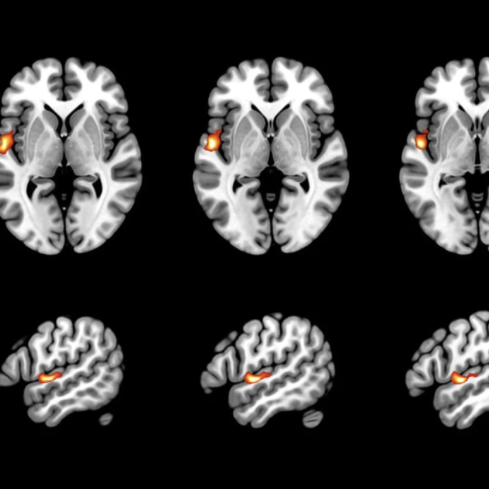

NEW PAPER: Fetal brain morphology as a predictor for language development. This study investigated the prognostic value of STS depth asymmetry in healthy fetuses for later language abilities, language localization, and language-related white matter tracts. Less right lateralization of the fetal STS depth was significantly associated with better verbal abilities, with fetal STS depth asymmetry explaining more than 40% of variance in verbal skills 6–13 years later. Furthermore, less right fetal STS depth asymmetry correlated with increased left language localization during childhood. (Lisa Bartha-Doering et al. Communications Biology 2023)

Fetal functional thalamo-cortical and cortico-cortical networks develop along specific trajectories. We modeled fetal functional thalamocortical connectome development using in-utero functional MRI in fetuses observed from 19th to 40th weeks of gestation. A peak increase of thalamo-cortical functional connectivity strength occurs between 29th and 31st GW, right before axons establish synapses in the cortex. The cortico-cortical connectivity increases in a similar time window, and exhibits significant functional laterality in temporal-superior, -medial, and -inferior areas. The similarity of homologous regions decreases during gestation giving way to a more diverse cortical interconnectedness. (Taymourtash et al. 2022 Cerebral Cortex)

Fetal functional brain networks emerge during gestation following a stabled timing. Region-specific increase of functional signal synchrony followed a sequence of occipital (peak: 24.8 GW), temporal (peak: 26 GW), frontal (peak: 26.4 GW), and parietal expansion (peak: 27.5 GW). (Jakab et al. 2014)